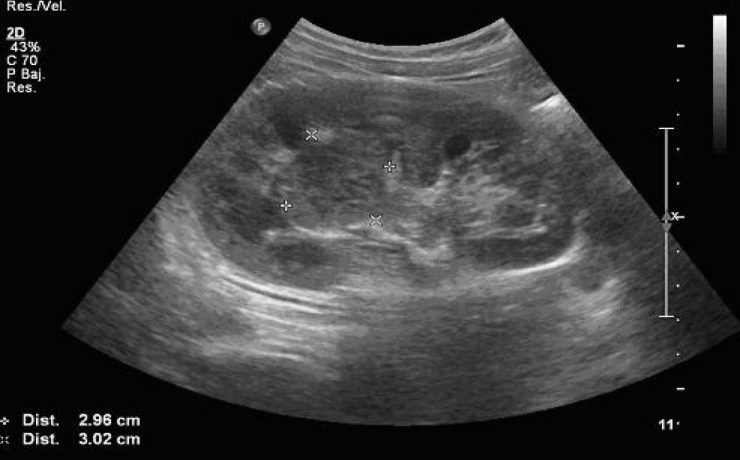

Durante el embarazo y la lactancia, la mama puede verse afectada por una variedad de trastornos únicos y específico, incluyendo trastornos benignos, relacionados con los cambios fisiológicos, inflamatorios, enfermedades infecciosas, papilomatosis juvenil y tumores benignos y malignos. Pacientes con carcinoma de mama asociada al embarazo presentan diagnóstico de neoplasias avanzadas y